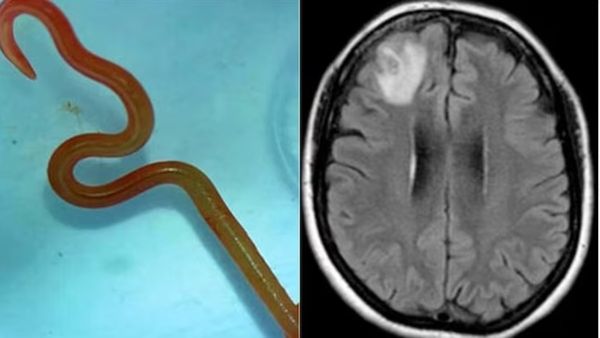

ವಿಶ್ವದ ಮೊದಲ ಕೇಸ್: ಆಸ್ಟ್ರೇಲಿಯಾ ರೋಗಿಯ ಮೆದುಳಿನಲ್ಲಿ ಜೀವಂತ ಹುಳ ಪತ್ತೆ: ಸ್ಕ್ಯಾನ್ ಕಂಡು ವೈದ್ಯರು ಶಾಕ್!

Tuesday, August 29, 2023, 12:23 [IST]